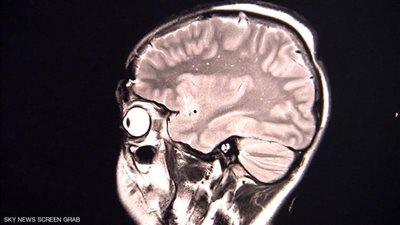

وجد باحثون أميركيون أن 3 مراهقين أصيبوا بأعراض نفسية نتيجة لعدوى "كوفيد-19" التي طالتهم، ورغم أن هذه الآثار تبدو نادرة، إلا أنها تدق ناقوس الخطر فهي سجلت في فئة يعتقد أنها في منأى عن الوباء. وأجرى باحثون في جامعة كاليفورنيا دراسات حالة على المراهقين الثلاثة لفحص كيفية حدوث هذه الأعراض.